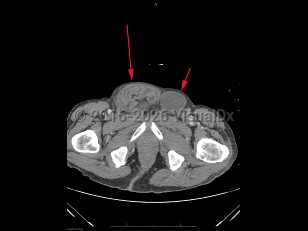

Inguinal hernia in Adult

An inguinal hernia is a protrusion of an intraabdominal organ, often the small bowel, through an opening in the inguinal area of the abdominal wall. Inguinal hernias are very common, occurring in approximately 5% of the general population. Risk factors include a personal / family history of hernias, history of prior hernia or hernia repair, advanced age, male sex, smoking, prior abdominal wall injury, chronic constipation, and chronic cough. Inguinal hernias can be congenital or acquired. They are caused by a weakening or failed closure of fibromuscular groin tissue.

Inguinal hernias can be classified as either direct or indirect, determined by their location. An indirect inguinal hernia's defect is at the internal inguinal ring. A direct inguinal hernia's defect is medial to the inferior epigastric vessels within Hesselbach's triangle. Indirect inguinal hernias are more common and are often attributed to congenital defects; direct inguinal hernias are often acquired in the setting of connective tissue weaknesses.